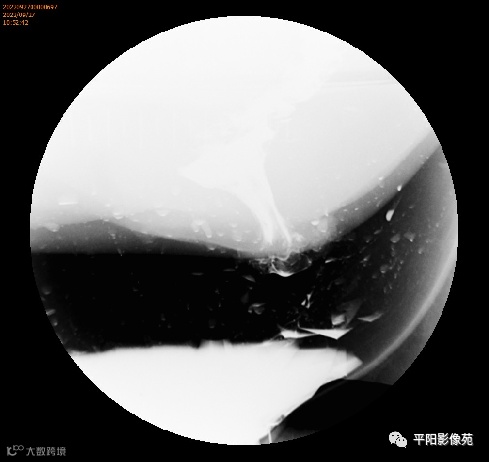

排粪造影

直肠壁部分或全层向下移位,称为直肠脱垂(rectal prolapse)

直肠壁部分下移,即直肠黏膜下移,称黏膜脱垂或不完全脱垂

直肠壁全层下移称完全脱垂

排便造影钡(x射线)排便造影或排便直肠造影是诊断排便障碍的公认临床

钡排粪造影实时评估直肠壁形态、盆底运动和排空。